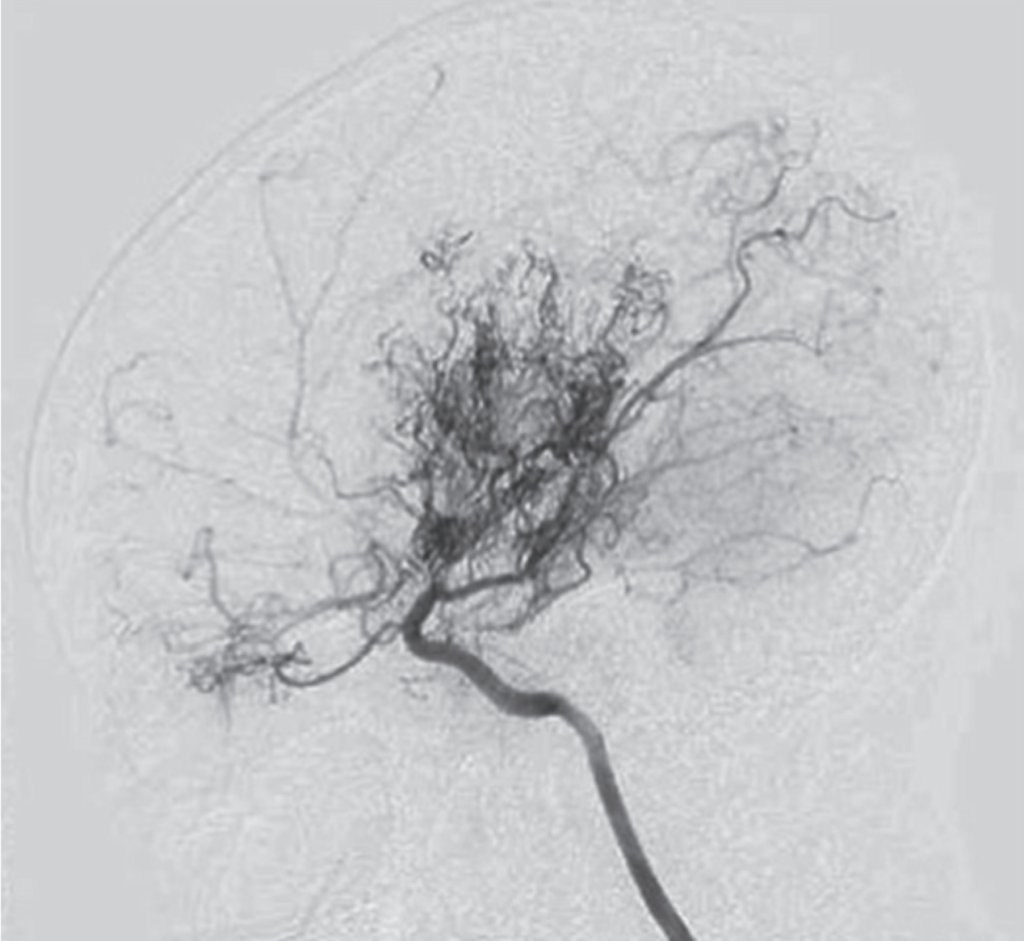

Digital Subtraction Angiogram (DSA) of the brain

Diagnosis is made using imaging studies such as MRI, MR Angiography, CT scans, and cerebral angiography, which evaluate blood flow and detect narrowing of brain vessels with formation of collaterals appearing as ‘Puff Of Smoke’. Special MRI scans are used to understand the blood flow to the brain.